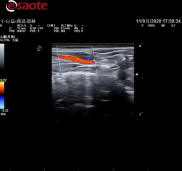

狗小肠

线阵探头

型号:SL3116

频率:10-22MHz

深度:15mm-44mm